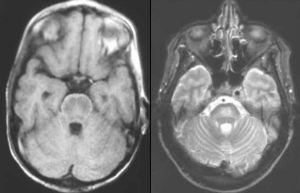

腦橋中央髓鞘溶解症影像圖流行病學

診斷:慢性酒精中毒、嚴重全身性疾病和低鈉血症糾正過快的患者,臨床上在數天之內突然發展為四肢癱瘓,假性延髓性麻痹和閉鎖綜合徵,就應考慮腦橋中央髓鞘溶解症的診斷。MRI有助於確診。實驗室檢查

本病應與腦橋基底部梗死、腫瘤和多發性硬化等鑑別。MRI顯示CPM無顯著占位效應,病灶對稱,不符合血管分布特徵,隨病情好轉可恢復正常。治療